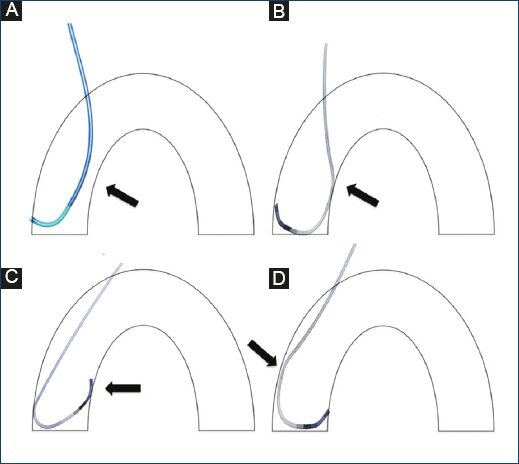

The Judkins traditional JL and JR catheters have good curvature and support for the femoral approach but do not transmit the same force when used in the transradial approach (Figs 5A-5D).

Figure 5 Diagram of the Judkins right coronary catheter in the right coronary ostium. Note the lack of support on the contralateral wall (A). Ikari left catheter in the right coronary ostium (B). Judkins left coronary catheter in the left coronary ostium. Note the absence of a landing zone on the ostium (C). Ikari left catheter on the left coronary ostium. Note the support on the contralateral wall when performed using the transradial approach (D).

As shown in Fig. 5, these properties improve backup support for the LCA. When used in the RCA, it may be used in a passive way as with the Judkins R. catheter. However, when more force is necessary, the contralateral aortic wall will increase backup support not provided by any other catheters as shown during in vitro studies16.